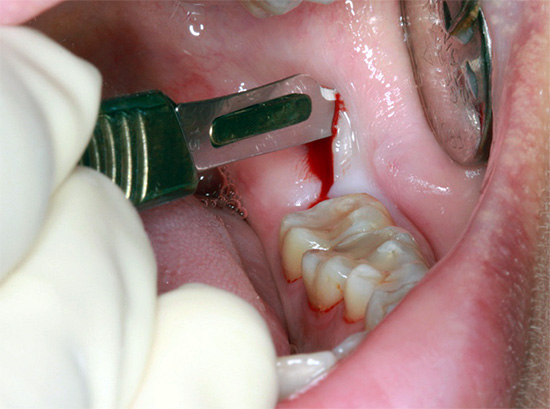

La foto sotto mostra le fasi iniziali della procedura per la rimozione del dente del giudizio retinirovannogo (cioè nascosto sotto la gomma):